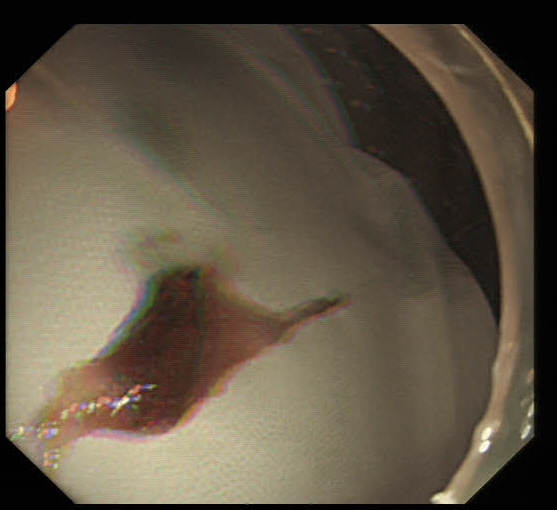

据北京世纪坛医院,4月25日深夜该院结直肠肿瘤外科李稳霞医师会诊了一位患者吴先生,两天前喝了大枣米粥后,出现左下腹疼痛。自己吃了家里常备的抗生素和胃药,就没当回事,结果后续肚子越来越疼。

经过检查发现,枣核尖卡在了小肠壁上,考虑肠穿孔、腹腔感染的可能性,立即进行了急诊手术。手术中医生发现小小的枣核一侧尖端已经将小肠壁刺穿,导致小肠局部穿孔,肠管周围还有少量的脓性渗出液。

北京世纪坛医院图